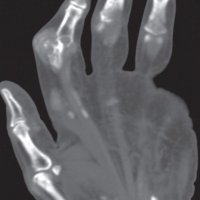

Trigger finger is a type of stenosing tenosynovitis. It develops due to repetitive microinjury from frequent flexion-extension movements of the fingers.

Primary trigger finger occurs most commonly in the middle fifth to sixth decades of life and up to 6 times more frequently in women than men.

A patient with trigger finger finds it difficult to straighten or bend the affected finger. The finger transiently gets locked in the flexed position and with a painful snapping sensation goes into extension.

Thickening and hyper-vascularization of the A1 pulley are the hallmarks of trigger fingers on sonography. Other frequently observed features include distal flexor tendinosis and tenosynovitis.

The first annular pulley (A1) at the metacarpal head is by far the most often affected pulley in trigger finger, though cases of triggering have been reported at the second and third annular pulleys (A2 and A3, respectively), as well as the palmar aponeurosis.

The level of thickening can be variable with some authors suggesting the normal value being around 0.5 mm with thickening suggested when the diameter is over 1.1 mm.

The condition can be conservatively managed with splinting, NSAIDs, and local steroid injections or may require a surgical section of the A1 pulley when the pulley is markedly thickened.